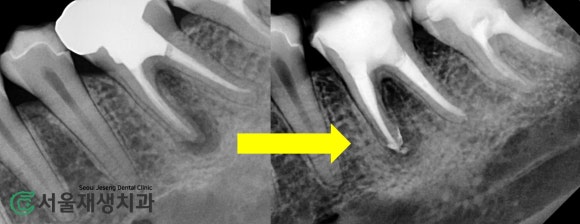

치료 전 후 사진

뿌리 끝까지

꼼꼼하게 치료되었습니다!